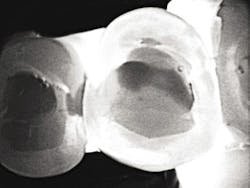

The third device, the CariVu caries detection device, uses a different type of science - near-infrared transillumination technology - to view carious lesions and cracks. Flexible "arms" on the device tip "hug" the tooth, and near-infrared photons are emitted through the arms to travel from the root to the crown of the tooth. Dense enamel reflects the photons, while porous lesions trap and absorb the photons. With the CariVu, healthy tooth appears light, and lesions appear dark. The CariVu is helpful in showing a structural view of the lesion, whether it's interproximal, occlusal, or proximal to restorations or a crack.

CariVu's diagnostic images have a high detection accuracy - an interproximal dentin caries detection rate of 99% with absolutely no ionizing radiation.1 While I take X-rays when they are necessary for a complete and effective diagnosis, CariVu helps when patients are: not due for bitewings, X-ray phobic, or reluctant to take X-rays because of a medical condition, such as radiation therapy. Because the CariVu images appear like radiographs, the patient can see the light areas of the healthy tooth and any dark, questionable, carious areas. They can see, along with me, whether I can wait to take X-rays until the next visit or whether I need to begin preventive or restorative treatment immediately. On these easy-to-read images, I can evaluate whether a carious lesion is starting or if the lesion is still in the "safe zone" (meaning it did not yet reach the dentinoenamel junction). Even if I find a questionable area on an X-ray - especially with possible interproximal decay, which can be difficult to detect, the "second opinion" of a transilluminated image can help me to determine the extent of the caries. For example, during a recent routine examination, the visual exam and radiographs did not reveal caries, but the CariVu found interproximal caries, necessitating restorative treatment.